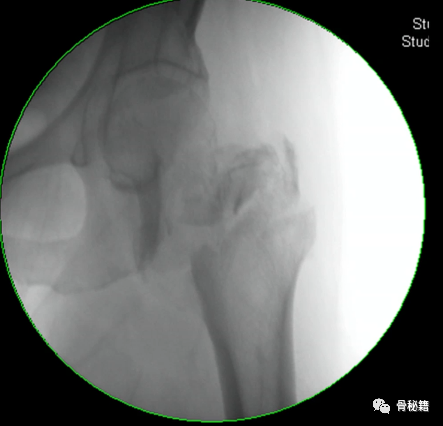

5、钉子的深度。逆行髓内钉的最佳深度是布鲁门萨线的顶点位置,正位居中

近端一般是小粗隆水平以上

6最后提一点锁钉的小技巧,不要造成主任打主钉5分钟,我们锁钉2小时。我们透视的时候,要把锁定空透成两个圆形,但是在操作中往往是椭圆形,这个时候根据椭圆形的长轴来方向来移动C臂,就可以透一个好的圆形了,在此情况下完成锁钉就相对容易些。